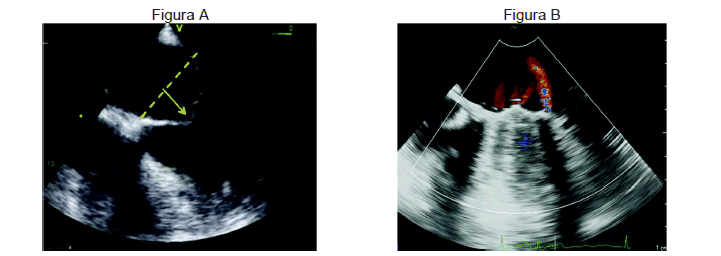

Paciente de 34 anos realizou ecocardiograma transesofágico no intraoperatório.

De acordo com as imagens apresentadas nas figuras A e B, ambas em sístole ventricular, é correto afirmar que a figura